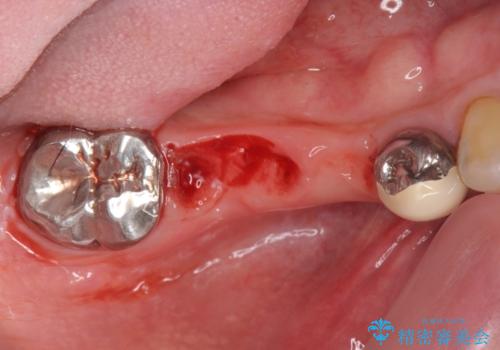

- 外科手術のため、術後に痛みや腫れ、違和感を伴います

設計に無理のある長期的に良好な状態が保てるとは思えないブリッジを除去し、インプラントを用いた補綴計画を立てます。